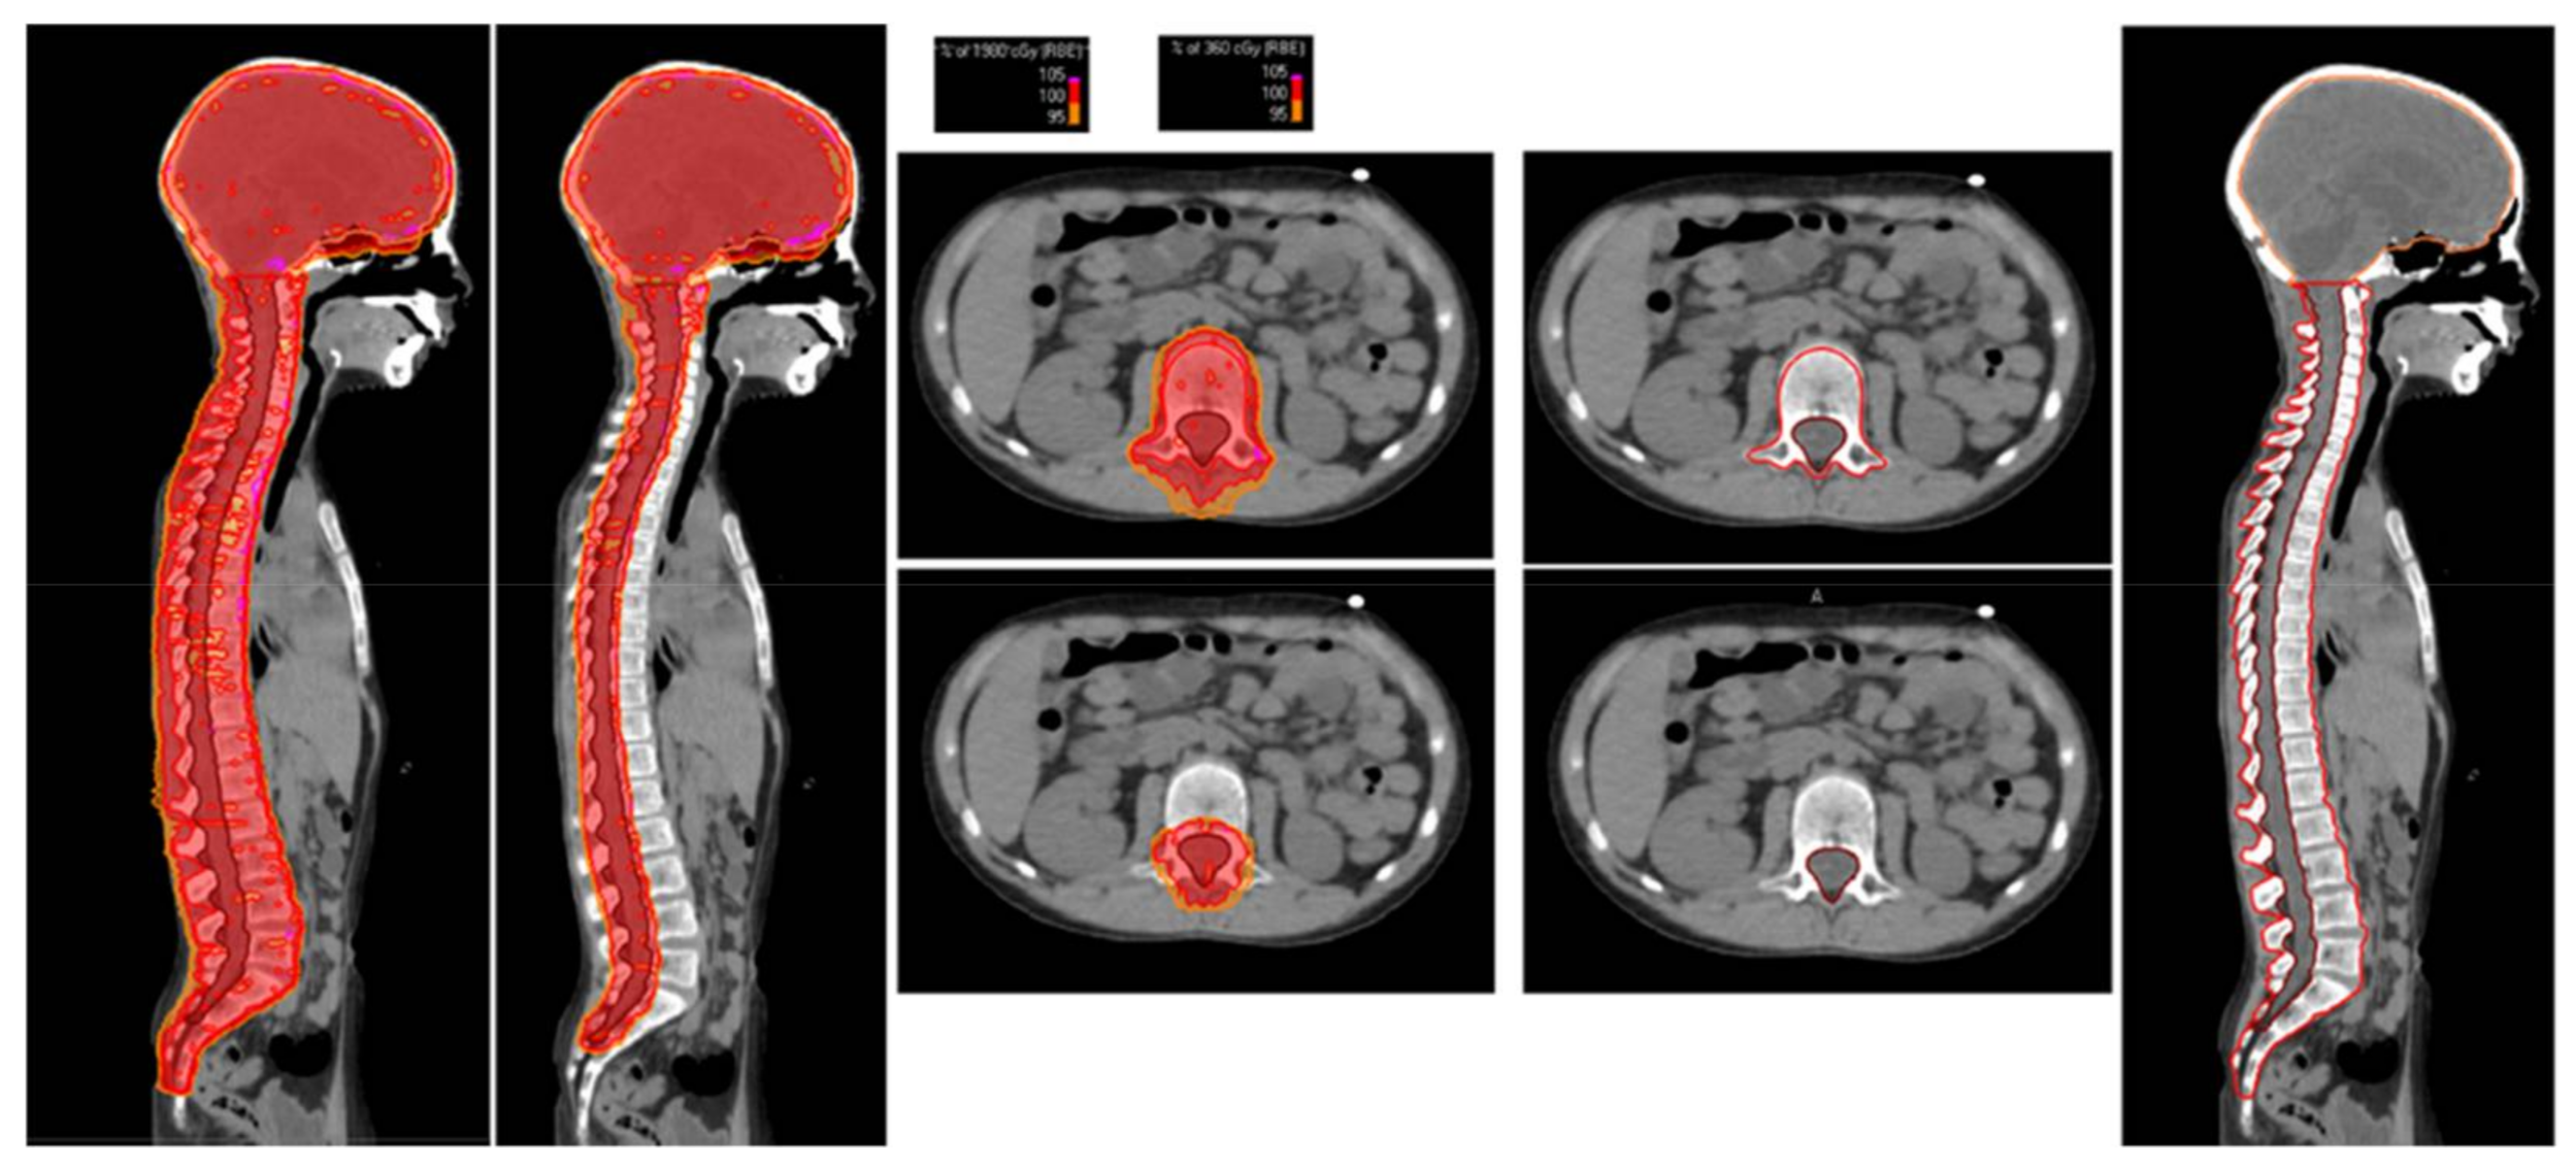

Patients were treated in a supine position using thermoplastic masks coupled with customized neck support and knee fixation support to guarantee immobilization during treatment. For all patients who had not completed skeletal maturity, namely patients ≤15 years of age (19 out of 20), in order to prevent uneven growth, a uniform dose to the entire vertebrae was administered; the clinical target volume (CTV) was represented by the whole brain, including the cribriform plate and the first third of the optic nerves as well as the entire spine, including the subarachnoid space, vertebral body, and spinal nerve roots; inferiorly, the edge of the CTV was set at the end of the thecal sac (usually at S2-S3 level). Our approach to CSI involved two steps of the dose (dual-phase) for the spinal region irradiation (Figure 1).

Figure 1.

The right side shows the target volumes drawn for the contouring of the CSI. The left side reports the dose distributions of the first phase (19.8 GyRBE to the brain plus the whole vertebral body) and the second phase (16.2 GyRBE to the brain plus the subarachnoid space and the spinal nerve roots) of the CSI.

All patients received a total CSI dose of 36 GyRBE. Those who had not reached skeletal maturity received the first 19.8 GyRBE (i.e., the first 11 treatment fractions of the CSI) to the entire vertebral body, while the remaining 16.2 GyRBE (i.e., the last 9 fractions of the CSI) were delivered only to the subarachnoid space and the spinal nerve roots. The planning target volume (PTV) was defined as a CTV expansion of 3 mm in the anterior-posterior direction and 5 mm in the latero-lateral and inferior-superior directions for the first treatment phase (up to 19.8 GyRBE), while for the second phase (the remaining 16.2 GyRBE) PTV was defined as a 5 mm isotropic expansion of the CTV.